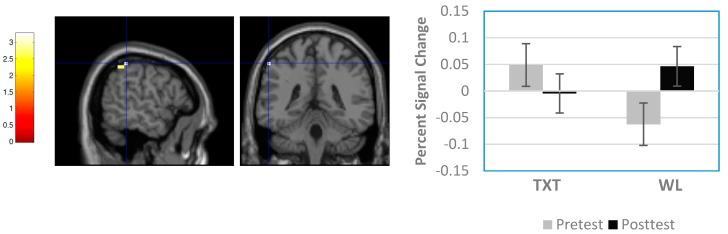

Children with fetal alcohol spectrum disorder (FASD) exhibit behavioral dysregulation, executive dysfunction, and atypical function in associated brain regions. Previous research shows early intervention mitigates these outcomes but corresponding brain changes were not studied. Given the Alert Program for Self-Regulation improves behavioral regulation and executive function in children with FASD, we asked if this therapy also improves their neural functioning in associated regions. Twenty-one children with FASD aged 8-12 years were randomized to the Alert-treatment (TXT; = 10) or waitlist-control (WL; = 11) conditions. They were assessed with a Go-NoGo functional magnetic resonance imaging (fMRI) paradigm before and after training or the wait-out period. Groups initially performed equivalently and showed no fMRI differences. At post-test, TXT outperformed WL on NoGo trials while fMRI in uncorrected results with a small-volume correction showed less activation in prefrontal, temporal, and cingulate regions. Groups also demonstrated different patterns of change over time reflecting reduced signal at post-test in selective prefrontal and parietal regions in TXT and increased in WL. In light of previous evidence indicating TXT at post-test perform similar to non-exposed children on the Go-NoGo fMRI paradigm, our findings suggest Alert does improve functional integrity in the neural circuitry for behavioral regulation in children with FASD.

患有胎儿酒精谱系障碍(FASD)的儿童表现出行为失调、执行功能障碍以及相关脑区的功能异常。先前的研究表明早期干预可减轻这些后果,但相应的脑变化尚未得到研究。鉴于自我调节警觉计划可改善FASD儿童的行为调节和执行功能,我们询问这种疗法是否也能改善他们相关脑区的神经功能。21名年龄在8至12岁的FASD儿童被随机分为警觉治疗组(TXT;n = 10)或等待名单对照组(WL;n = 11)。在训练前后或等待期结束后,他们接受了一项停止信号功能磁共振成像(fMRI)范式评估。两组最初表现相当,fMRI结果无差异。在测试后,TXT组在停止信号试验中的表现优于WL组,而在未校正结果并进行小体积校正的fMRI显示,前额叶、颞叶和扣带区域的激活较少。两组还表现出不同的随时间变化模式,反映出TXT组在测试后选择性前额叶和顶叶区域的信号减少,而WL组增加。鉴于先前的证据表明,在停止信号fMRI范式中,测试后的TXT组表现与未接触该疗法的儿童相似,我们的研究结果表明,警觉计划确实能改善FASD儿童行为调节神经回路的功能完整性。